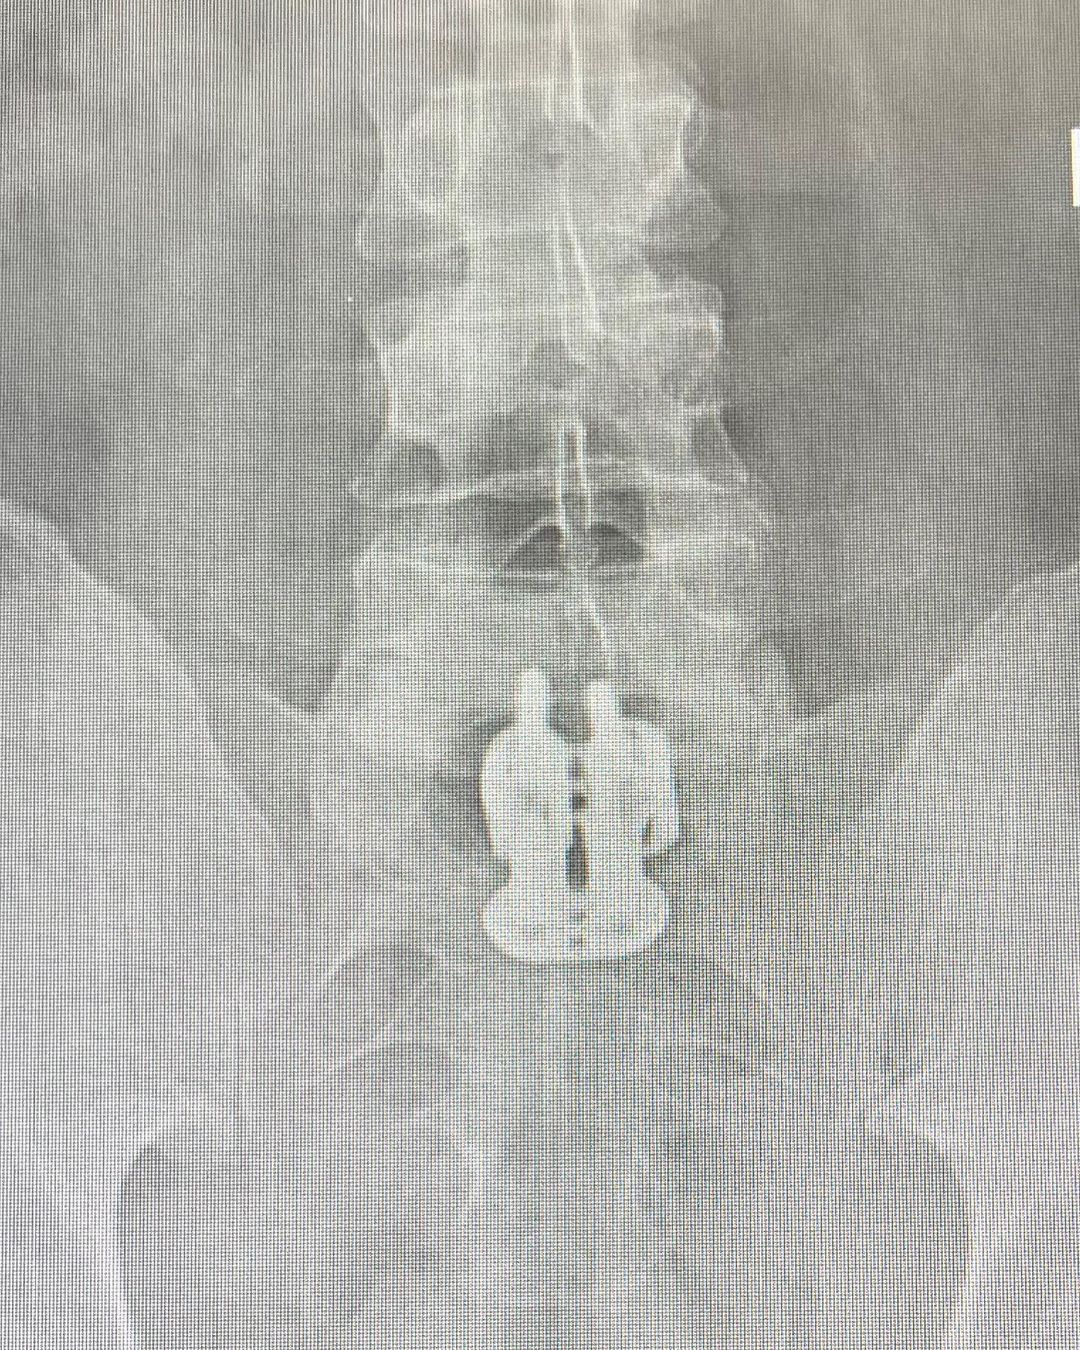

Hello. Quick update- I had my 1st post spine fusion surgery check up today with @andrewhechtmd & everything looks great. Also, we found the missing pieces from our nativity scene! (This is the actual X-ray photo) 😇